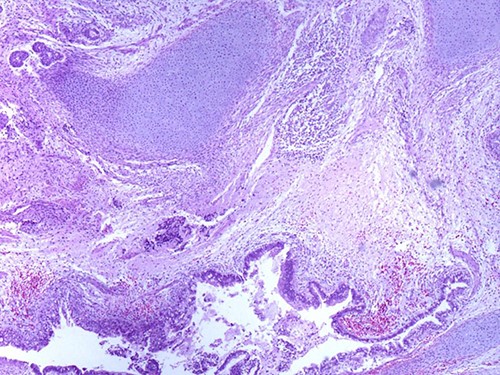

A 46-year-old woman, without clinical antecedent, presented with a tumor in the inner side of the left cheek which had rapidly grown for 3 weeks. Physical examination revealed an ulcerating mass measuring 4 × 3.5 cm, well-circumscribed, fleshly, with a white surface. There was submandibular lymphadenopathy, ranging in dimension from 1 to 1.5 cm in diameter. Magnetic resonance imaging (MRI) scan revealed the tumor of the cheek without mandibular bone infiltration or sinonasal involvement (Fig. 1). Chest computed tomography and abdominal ultrasound scan were unremarkable. An excisional biopsy was performed. Pathological examination showed a neoplastic proliferation composed of mixture of mature benign epithelial components, such as intestinal type, respiratory and squamous epithelia, and mature mesenchymal components, such as muscular tissue and cartilage (Fig. 2) and neuroglial tissue. In addition, immature and malignant tumor components were found such as small blue tumor cells resembling primitive neuroectodermal tumor (Fig. 3), adenocarcinoma and sarcoma with muscular and cartilaginous differentiation (Fig. 4). This tumor infiltrates the skeletal muscle with free margins. Immunohistochemically, epithelial components were positive for pankeratin; mesenchymal components showed desmin, myogenin and S-100 positivity and the primitive neuroectodermal tumor component was positive for NSE, CD99, GFAP, synaptophysin and focally for chromogranin. SALL4 was negative. The resected submandibular lymph nodes were devoid of malignant infiltrate. The diagnosis of TCS was established and the patient was treated by combined chemotherapy (cisplatine +5 fluorouracil) and radiation therapy. No recurrence was noted 6 months after treatment.

Photomicrograph of carcinomatous component (magnification at ×400).